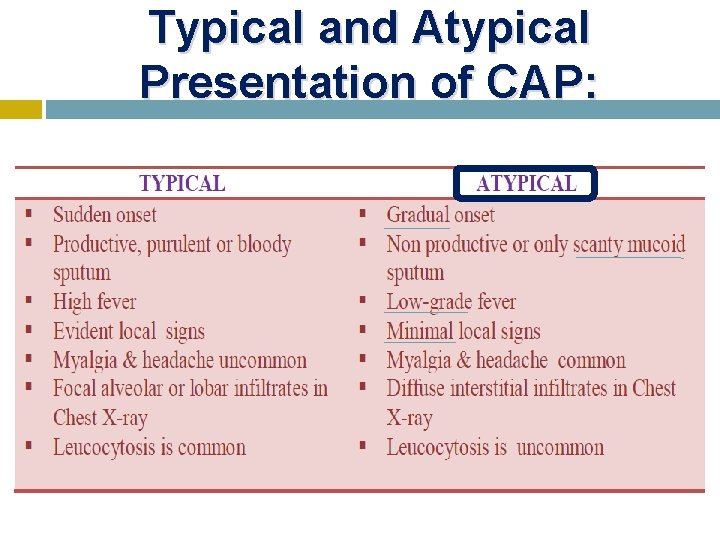

Typical and Atypical Presentation of CAP: